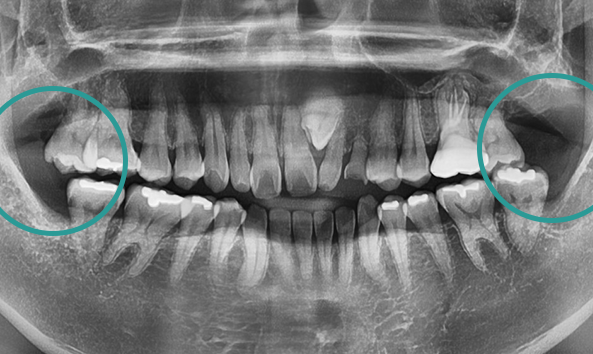

골치 아픈 사랑니, 대학병원 가지 않으셔도 됩니다.

사랑니는 기형적으로 맹출되거나

잇몸 속에 매복되는 경우가 많아 발치가 까다로울 수 있습니다.

특히, 인접 치아를 손상시키지 않고 신경을 보호하며 발치하려면

전문적인 노하우가 필수입니다. 그래서 사랑니 발치는 많은 고민과 망설임을 동반하는

어려운 선택이 될 수 있습니다. 올디플란트치과는 이런 걱정을 덜어드릴 자신이 있습니다.

사랑니 발치를 위해 치과를 찾아 헤매고 계신가요?

매복 사랑니는 신경과 가까워 발치 시

신경 손상의 위험이 높아

일부 동네 치과에서는 치료를 권하지 않기도 합니다.

하지만 올디플란트치과는

대학병원 가기 전에 방문하는 치과로 유명하며,

타원에서 발치하지 못한 케이스도

책임지고 해결해드리고 있습니다.